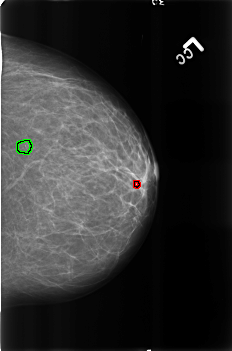

B_3165_1.LEFT_CC

LEFT_CC LINES 4552 PIXELS_PER_LINE 3016 BITS_PER_PIXEL 12 RESOLUTION 50 OVERLAY

FILE: B_3165_1.LEFT_CC.OVERLAY

TOTAL_ABNORMALITIES 2

ABNORMALITY 1

LESION_TYPE CALCIFICATION TYPE LUCENT_CENTERED DISTRIBUTION N/A

ASSESSMENT 2

SUBTLETY 4

PATHOLOGY BENIGN

TOTAL_OUTLINES 1

BOUNDARY

ABNORMALITY 2